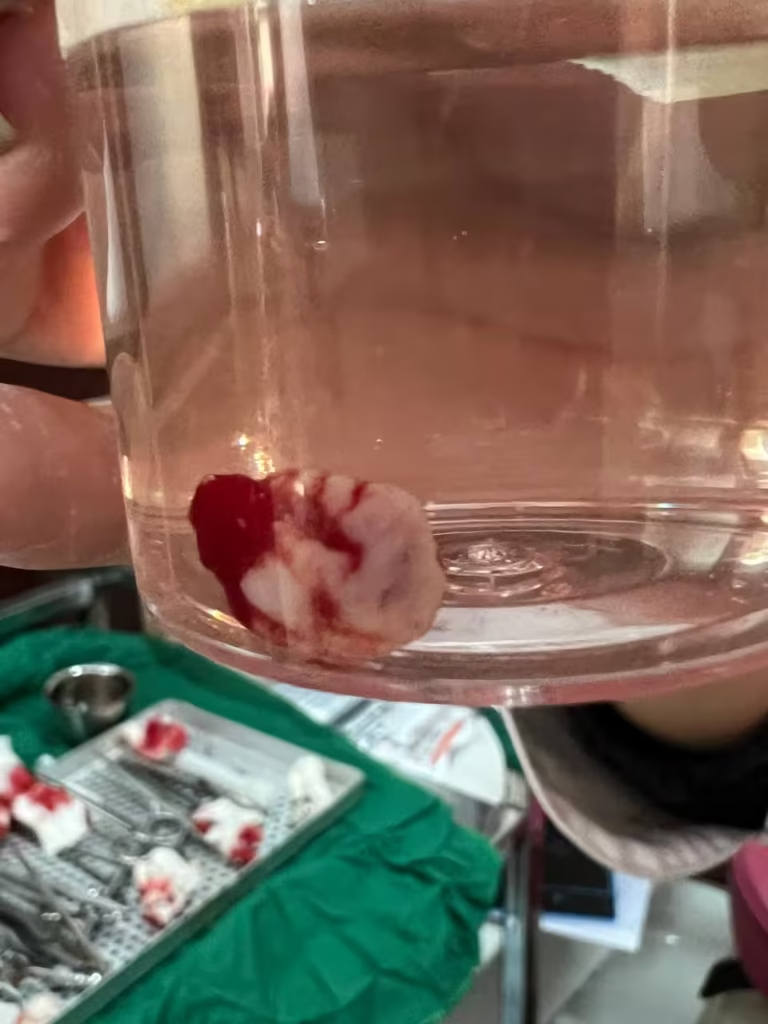

جراحی

· برداشت تومور با حاشیه سالم پرکاربردترین روش در مراحل اولیه است. جراح فک و صورت بافت سرطانی را همراه با بخش کوچکی از بافت سالم اطراف آن برمیدارد تا احتمال عود به حداقل برسد. هرچه اندازه ضایعه کوچکتر باشد میزان کمتری از بافت برداشته میشود و زیبایی و عملکرد ساختارهای دهانی و صورتی کمتر به خطر میافتد.

بسیاری از افراد آگاه برای انجام معاینات و غربالگری سالانۀ سرطان دهان یا با مشاهدۀ یک ضایعۀ دهانی برای ارزیابی دقیقتر به ما مراجعه میکنند. در مرکز ما ابتدا معاینات کامل و جامع خارجدهانی و داخلدهانی توسط متخصص بیماریهای دهان انجام میشوند. درصورت مشاهدۀ ضایعات مشکوک، اعم از زخمها، ضایعات سفید و قرمز یا برجسته و تودهمانند، از ضایعه نمونهای تهیه شده و برای بررسی میکروسکوپی به مرکز پاتولوژی فرستاده میشود. گاهی اوقات قبل از انجام نمونهبرداری لازم است ناحیه مد نظر با مواد رنگی مخصوصی رنگآمیزی شود تا نواحی مشکوکتر برای نمونهبرداری انتخاب شوند.

بعد از اینکه نتیجۀ پاتولوژی مشخص شد و تشخیص نهایی ضایعه گذاشته شد، بر اساس نوع ضایعه، وجود یا عدم وجود تغییرات سلولی، گسترش سرطان و… دربارۀ مراحل بعدی تصمیمگیری میشود. در این مرحله، گاهی اوقات انجام رادیوگرافیهای تخصصی سر و گردن، مثل سیتیاسکن، امآرآی یا سونوگرافی، ضرورت پیدا میکند. بر اساس نوع ضایعه، گاهی انجام آزمایشات تکمیلی خون نیز درخواست میشود. درصورت تشخیص ضایعات پیشسرطانی، بیمار تحتنظر متخصص بیماریهای دهان قرار گرفته و بهصورت دورهای معاینه میشود تا درصورت مشاهدۀ کوچکترین تغییرات، اقدامات لازم انجام شوند. در برخی موارد، تصمیم به حذف ضایعات با لیزر، فتودینامیک تراپی یا درمانهای دارویی گرفته میشود. اما باید توجه کرد که حتی با حذف تمام ضایعات، معاینات دورهای منظم حتماً باید انجام شوند؛ چراکه احتمال بروز ضایعات مشابه یا سرطان دهان در همان نقطه یا سایر نقاط دهان در این بیماران وجود دارد. درصورت تشخیص سرطان، ضایعۀ دهانی همراه با یک حاشیۀ سالم توسط جراح فک و صورت و معمولاً در بیمارستان برداشته میشود. درخصوص برخی ضایعات بزرگتر که انجام جراحی میتواند باعث از دست رفتن بخش قابل توجهی از بافت دهانی یا عملکرد بیمار شود، پس از مشاوره با انکولوژیست قبل از درمان جراحی، رادیوتراپی یا شیمیدرمانی انجام میشود تا سایز توده کوچکتر شده و برداشت جراحی آن با برداشت بافت کمتری همراه باشد.